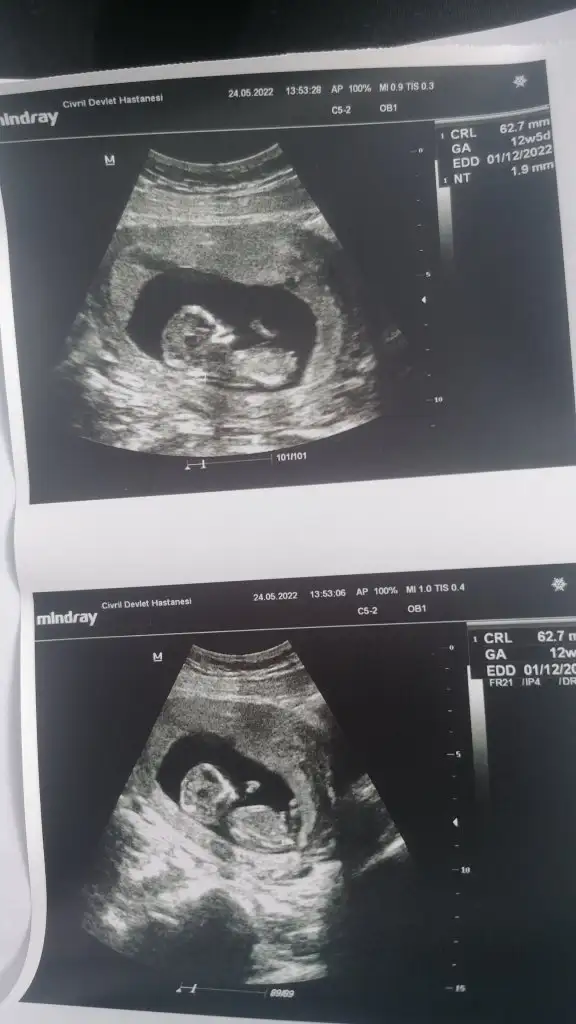

Ramzi teorisine göre cinsiyet tahmini yapacagim ilk ultrasyon resminizi atin bakiyim. Eger cinsiyetiniz belliyse hic söylemeeyin bakalm dogru tahmin edebilecekmiyim daha dogrusu ramzi teorisi hakli cikacak mi?

Canim ilk ultrasonunu at 6-7-8Merhaba arkadaşlar. Karın ultrasonu 12+3 Ramziye bakılabiliyor mu bilmiyorum ama benim içinde tahminde bulunabilir misiniz? Eki Görüntüle 3071869